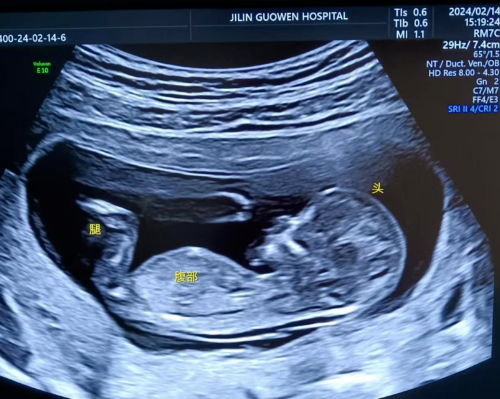

寶媽看過來! 胎兒NT彩超免費檢查長春國文醫(yī)院支持國家優(yōu)生優(yōu)育政策,回饋寶媽,NT彩超檢查免費。那么,什么是NT檢查呢?

NT 檢查是一種在孕期進行的重要檢查項目,全稱為頸項透明層檢查,以下是關于它的詳細介紹:

通常在懷孕 11 周 - 13 周 + 6 天之間進行。這個時期胎兒大小適中,頸項透明層的顯示較為清晰,測量結果也相對準確,能更好地發(fā)揮 NT 檢查對胎兒異常的篩查作用。

超聲檢查,孕婦無需空腹。檢查時,超聲醫(yī)生會使用超聲儀器對胎兒頸部進行仔細觀察和測量。通過超聲探頭可以清晰地看到胎兒在子宮內(nèi)的情況,重點測量胎兒頸項部皮下無回聲透明層最厚的部位,測量值即為 NT 值。正常胎兒 NT 值一般不超過 2.5mm。